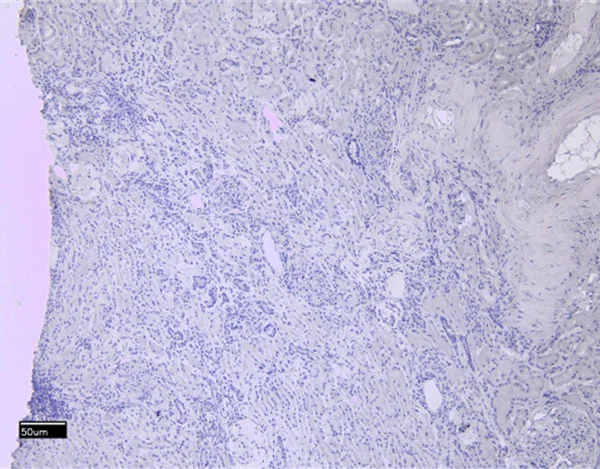

| EB05117 | Goat Anti-ITK Antibody | Pep-ELISA, WB, IF | Human, Mouse | 100µg/200µl |

| EB08802 | Goat Anti-ITK Antibody | Pep-ELISA, WB, IHC, IF, FC | Human, Rat, Cow | 100µg/200µl |